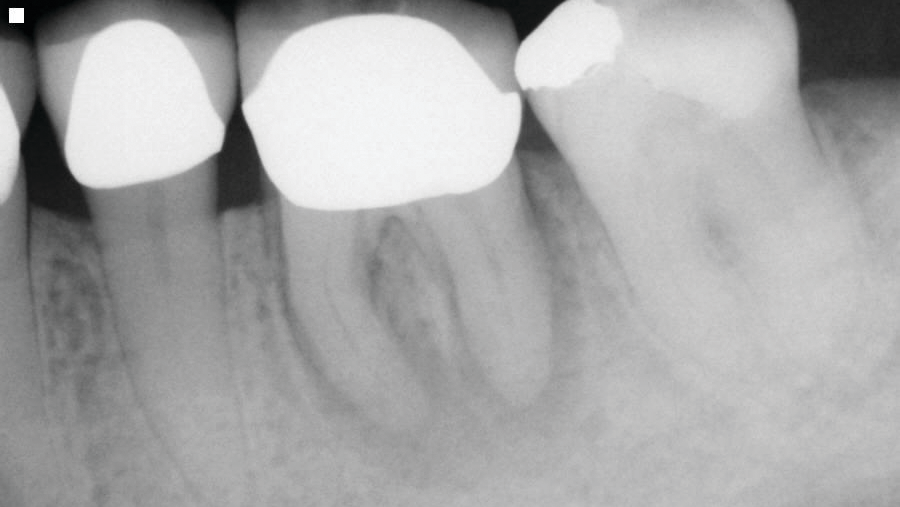

The second case involves a patient with tooth no. 19 having substantial furcation damage and moderate-sized apical periodontitis (figure 3).

Treatment included a two-visit approach, with two weeks in interim calcium hydroxide therapy.